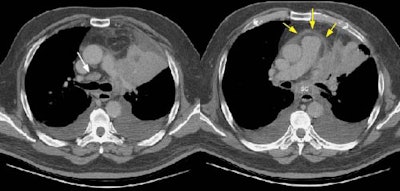

Example 1: False-positive exam -- this patient had a right upper lobe squamous-cell carcinoma. The mass is adjacent to the superior vena cava. Abnormal mediastinal N2 (yellow arrow) nodes were identified by the staging CT exam. Contralateral N3 nodes (white arrows) were borderline abnormal by size criteria. The patient underwent medianstinoscopy and anterior mediastinotomy (Chamberlain procedure) for pre-operative staging -- both of which were negative for malignant cells. The patient had underlying interstitial lung disease which has been associated with the presence of reactive mediastinal adenopathy. At surgery the patient was found to have ipsilateral hilar adenopathy (N1) and parietal pleural invasion (T3 tumor) or a stage IIIA.

Example 2: False-negative CT exam -- this patient had an adenocarcinoma in the right upper lobe that measured less than 3 cm in size (T1 lesion). The ipsilateral mediastinal nodes identified by staging CT were not pathologic by size criteria. The surgical team elected to proceed to thoracotomy without mediastinoscopy. At surgery, the small right paratracheal nodes which measured less than 1 cm where found to contain microscopic foci of tumor (N2 nodes). The patient was staged histopathologically as T1N2M0 (Stage IIIA).